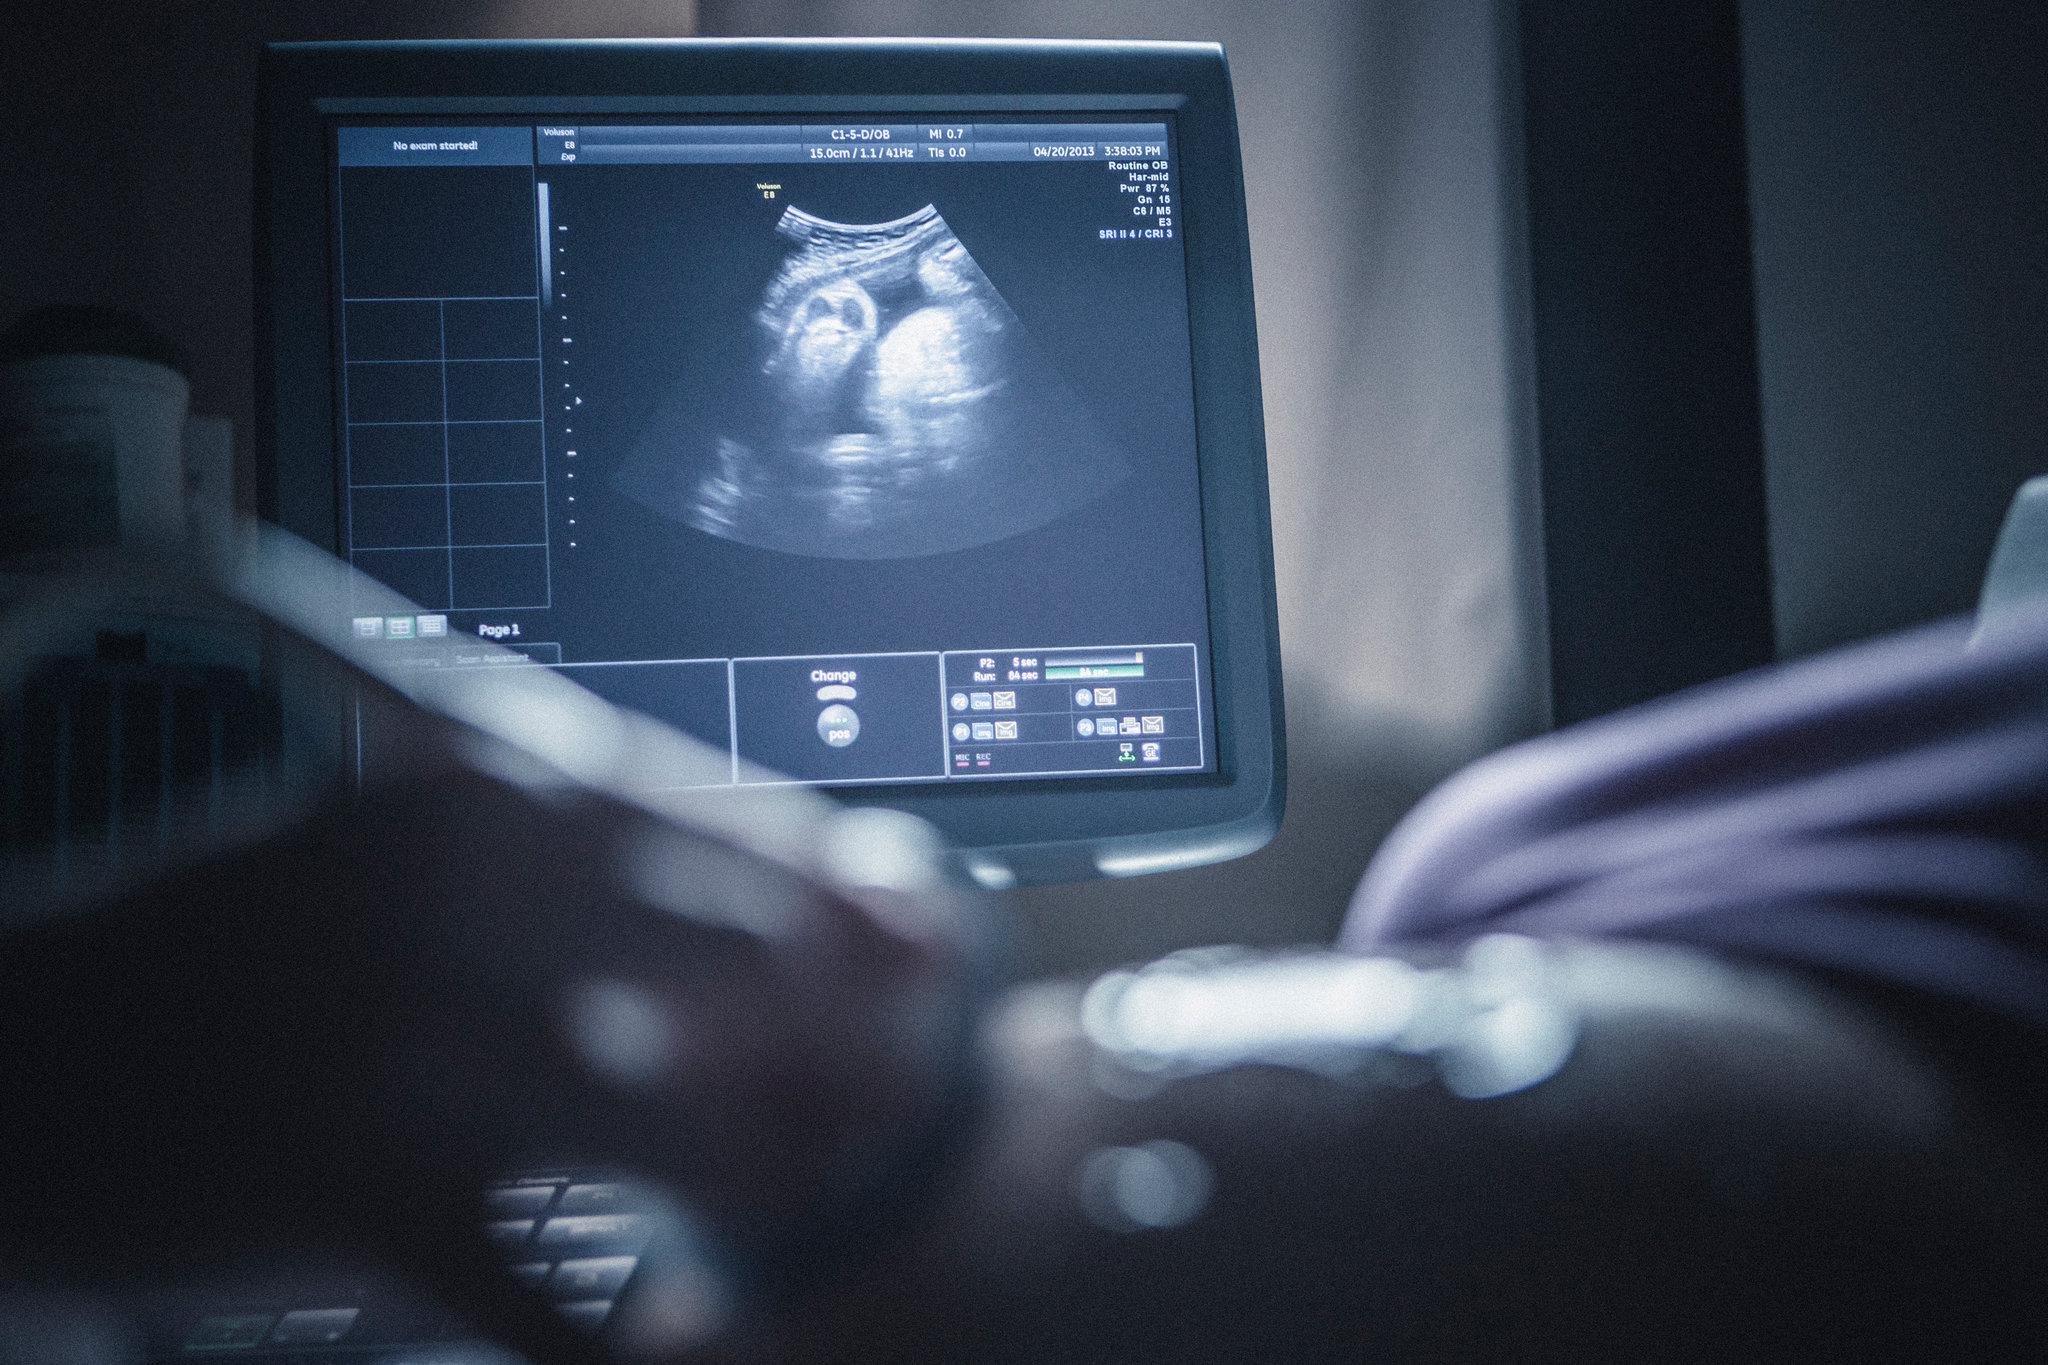

در طول اسکن NT، یک دستگاه کوچک دستی که امواج صوتی منتشر میکند توسط پزشک روی شکم شما مالیده میشود. این امواج از جنین منعکس شده و به دستگاه سونوگرافی منعکس میشوند و تصویری روی صفحه نمایش از جنین و رحم شما ایجاد میکنند.

سونوگرافی اولیه (که سونوگرافی سه ماهه اول نیز نامیده می شود). سونوگرافی از امواج صوتی و صفحه نمایش کامپیوتر برای ایجاد تصویری از جنین در داخل رحم استفاده می کند. ارائه دهنده شما ممکن است از سونوگرافی زودهنگام برای اطمینان از باردار بودن یا تعیین تاریخ بارداری خود استفاده کند تا بدانید در طول بارداری (چند هفته) هستید.

سونوگرافی

سونوگرافی معمولا در دوران بارداری انجام می شود. هیچ خطر شناخته شده ای برای زن یا جنین ندارد. سونوگرافی می تواند کارهای زیر را انجام دهد: